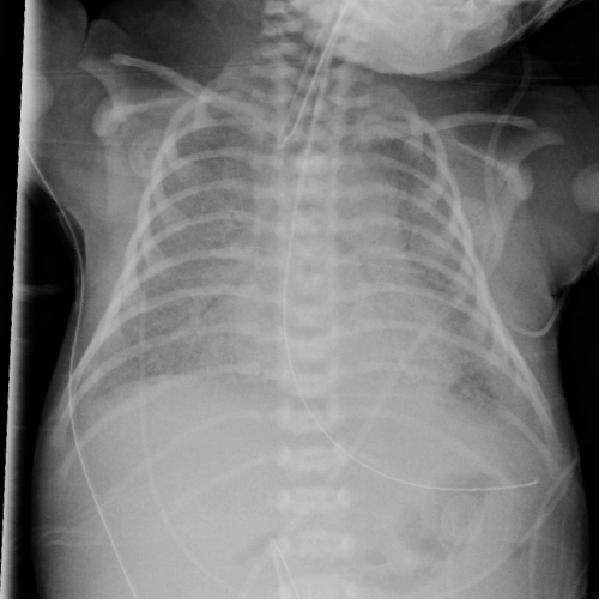

2、新生儿在剖腹产后数小时内出现呼吸困难。

仍可见双侧对称弥漫分布的的颗粒状高密度影,支气管充气征。

这就是典型的新生儿特发性呼吸窘迫综合征(RDS)。

其特征性 X 线表现为:

1)两肺野透光度普遍减低,呈毛玻璃状,或两肺野中内带多发细小颗粒状或小结节和网状影,下肺野较上肺野更为显著;

2)气管支气管充气显著,在两肺野密度普遍性增加的对比之下显示更为清楚;

3)胸廓扩张良好,横膈位置正常。 对怀疑本病者,短期(1 ~ 2h)连续拍片观察,对诊断意义较大;有文献提出凡 6~ 12h 胸部影像尚无确切网粒阴影者,可排除本病。